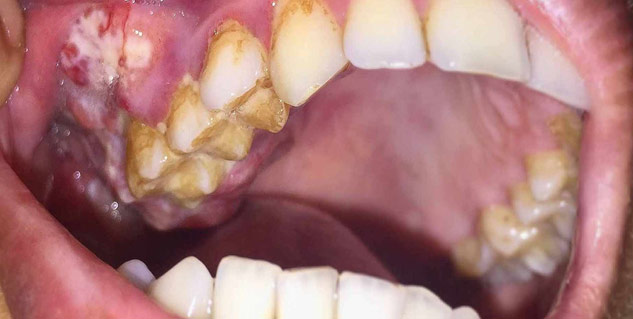

1. मुंह का कैंसर या ओरल कैंसर (Oral Cancer)

खराब ओरल हाइजीन की वजह से दांतों में सड़न होने लगती है, जो कैविटी का कारण बनती है। कैविटी की वजह से पेरिएपिकल संक्रमण (periapical infection) हो जाता है और गैर-महत्वपूर्ण दांत टूट जाते हैं। ये टूटे दांत मुंह के म्यूकोसा में पुरानी जलन का स्त्रोत हो सकते हैं और मुंह के कैंसर या ओरल कैंसर का कारण बन सकते हैं।

दांतों की सफाई न करना या ओरल हाइजीन का ध्यान न रखने की वजह से पीरियोडोनाइटिस की समस्या भी हो सकती है। इसमें पुरानी सूजन या क्रॉनिक इंफ्लामेशन oral epithelium के घातक परिवर्तन का खतरा हो सकता है।

ओरल प्लेक्यू (oral plaque) और पथरी (calculus) क्रॉनिक इंफ्लामेशन और इरिटेशन पैदा कर सकता है। कुछ बैक्टीरिया जैसे हेलिकोबैक्टर पाइलोरी ( Helicobacter pylori ) और पोर्फिरोमोनस जिंजिवलिस (Porphyromonas gingivalis) मौखिक उपकला को उपनिवेशित करते हैं, विभिन्न कैंसर से जुड़े हुए हैं। पीरियोडोनाइटिस के रोगियों (periodonitis) की मौखिक गुहा में जीवाणु प्रजातियां नाइट्रेट को नाइट्राइट में बदल देती हैं या एसिटालडिहाइड का उत्पादन करती हैं, जो सभी कार्सिनोजेनिक मेटाबोलाइट्स हैं।